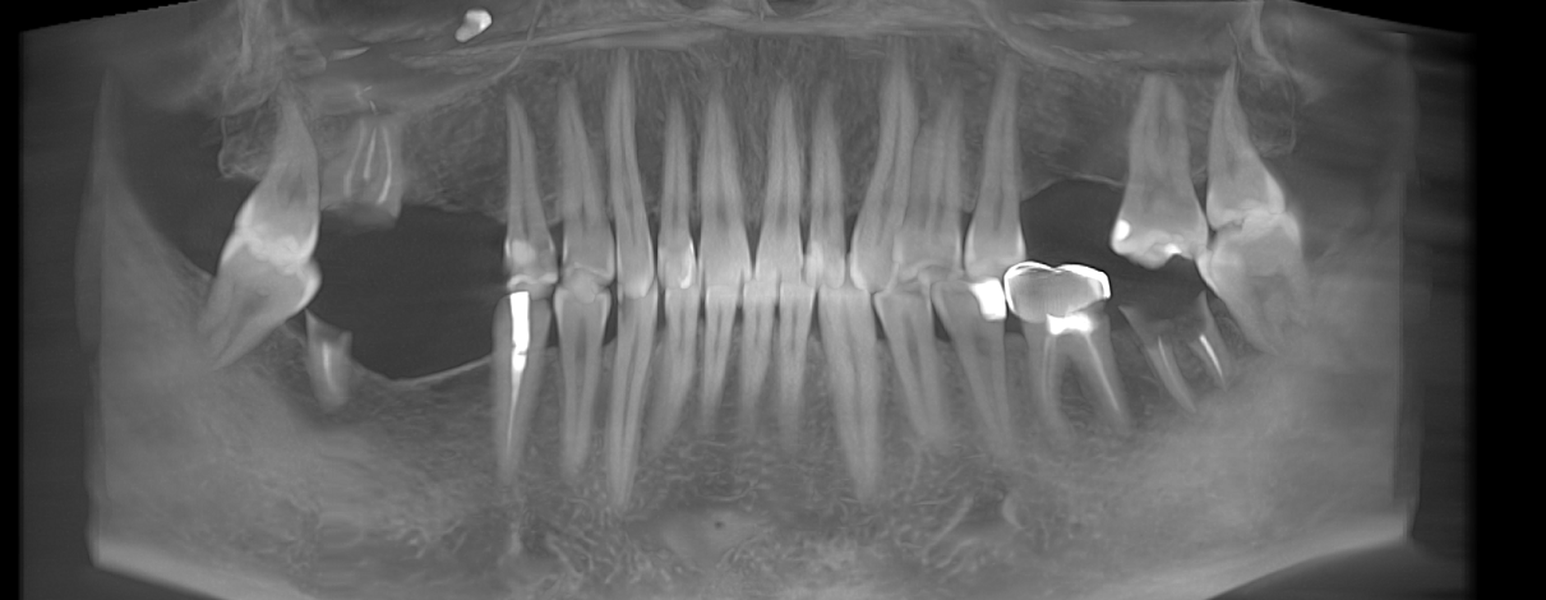

- Consultația inițială și planificarea tratamentului (inclusiv tomografie CBCT)

- Inserarea implanturilor dentare (chirurgie ghidată digital)

- Perioada de osteointegrare (3–6 luni)

După inserarea unui implant dentar – o rădăcină artificială din titan sau zirconiu –, urmează etapa de protezare, adică atașarea unei structuri protetice (coroană, punte sau proteză) care înlocuiește dintele lipsă.